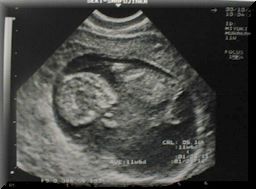

00/09/29 7週目 | ![]() | 1.5cm | ![]() |